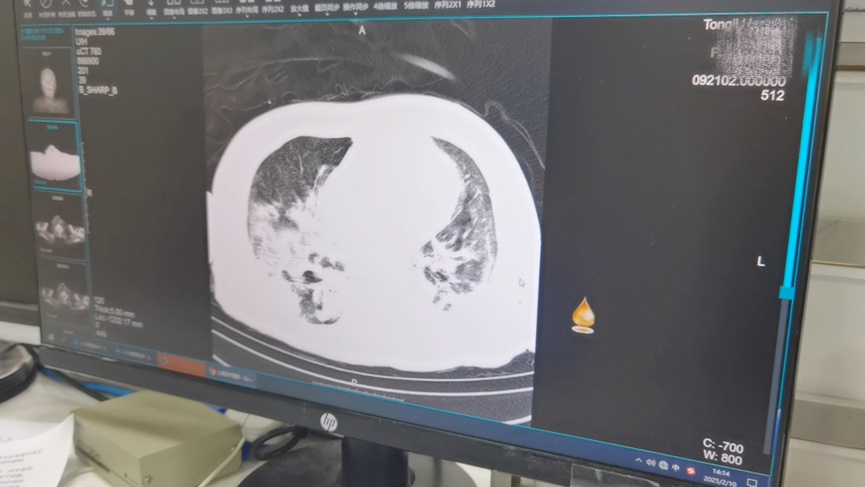

患者老杜,因高热、胸闷、气急等症状来急诊就诊,血氧饱和度89%,C反应蛋白和降钙素原提示严重感染,胸部CT示:两肺炎症,为进一步治疗,收治入EICU。入科后给予抗感染、抗病毒治疗,高流量辅助通气,但情况未见好转。1天后,老杜用上了呼吸机,肺部炎症加重,调整抗生素,进行NGS培养,俯卧位通气……一系列的措施后老杜的情况稍稍稳定下来。2天后,老杜的病情迅速恶化,CT显示两肺“白化”,出现严重的呼吸功能衰竭,氧饱和度在呼吸机纯氧的情况下,仍只能维持在84%-90%,更严重的是,老杜出现了多器官功能衰竭及严重的电解质紊乱,生命危在旦夕。